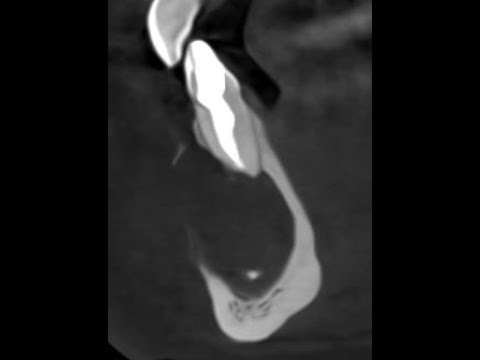

Размеры гнойного мешочка могут не превышать нескольких миллиметров, но на рентгеновских снимках резидуальные кисты хорошо просматриваются. Пока пораженный участок невелик, пациент не испытывает никакого дискомфорта, по мере роста кисты могут отмечаться выпуклые образования округлой формы, лицевая стенка челюсти при этом истончается.

Зачастую пациентам после неправильного удаления зуба вновь приходиться идти на прием к стоматологу, у них развивается резидуальная киста. Рентгеновское обследование позволяет увидеть прозрачную полость, которая находится в той области, где ранее был удален зуб. По своим клиническим и гистологическим характеристикам резидуальная киста схожа с радикулярной.

Если кистозное образование на верхней или нижней челюсти становится больших размеров, как видно на фото выше, это приводит к нарушению прикуса, разрушению пульпы зуба, расшатыванию соседних зубов. Профилактика заключается в регулярном посещении стоматолога и соблюдении правил личной гигиены.